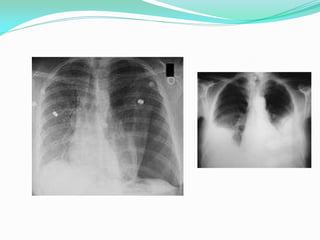

Las pleuras son membranas serosas que recubren los pulmones y la pared torácica interna, y el espacio pleural es el espacio entre ambas pleuras que contiene una pequeña cantidad de líquido lubricante. Las pleuras se relacionan íntimamente con la pared torácica permitiendo el movimiento respiratorio, y la radiología como las placas de tórax y la tomografía computarizada proporcionan imágenes del espacio pleural y sus relaciones.